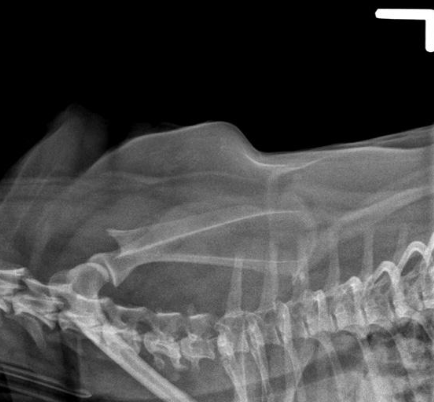

what view of the scapula is shown?

lateral view